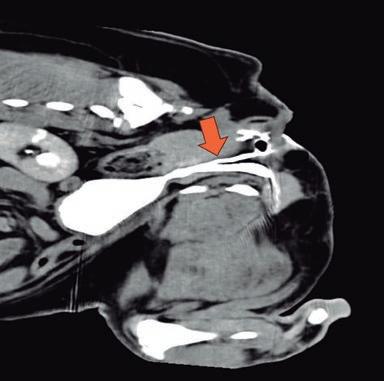

Agujas de acceso vascular